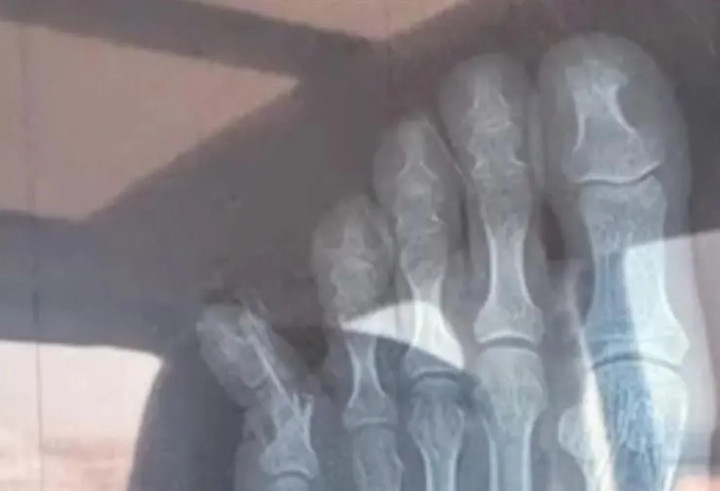

Ảnh chụp X-quang của Trương. (Ảnh: Baidu)

Kết quả chụp X-quang thể hiện rõ Trương bị gãy xương. Cô phải băng bó cả bàn chân. Sau khi sự việc xảy ra, Trương đăng ký cho con trai vào một lớp học thêm sau giờ học.